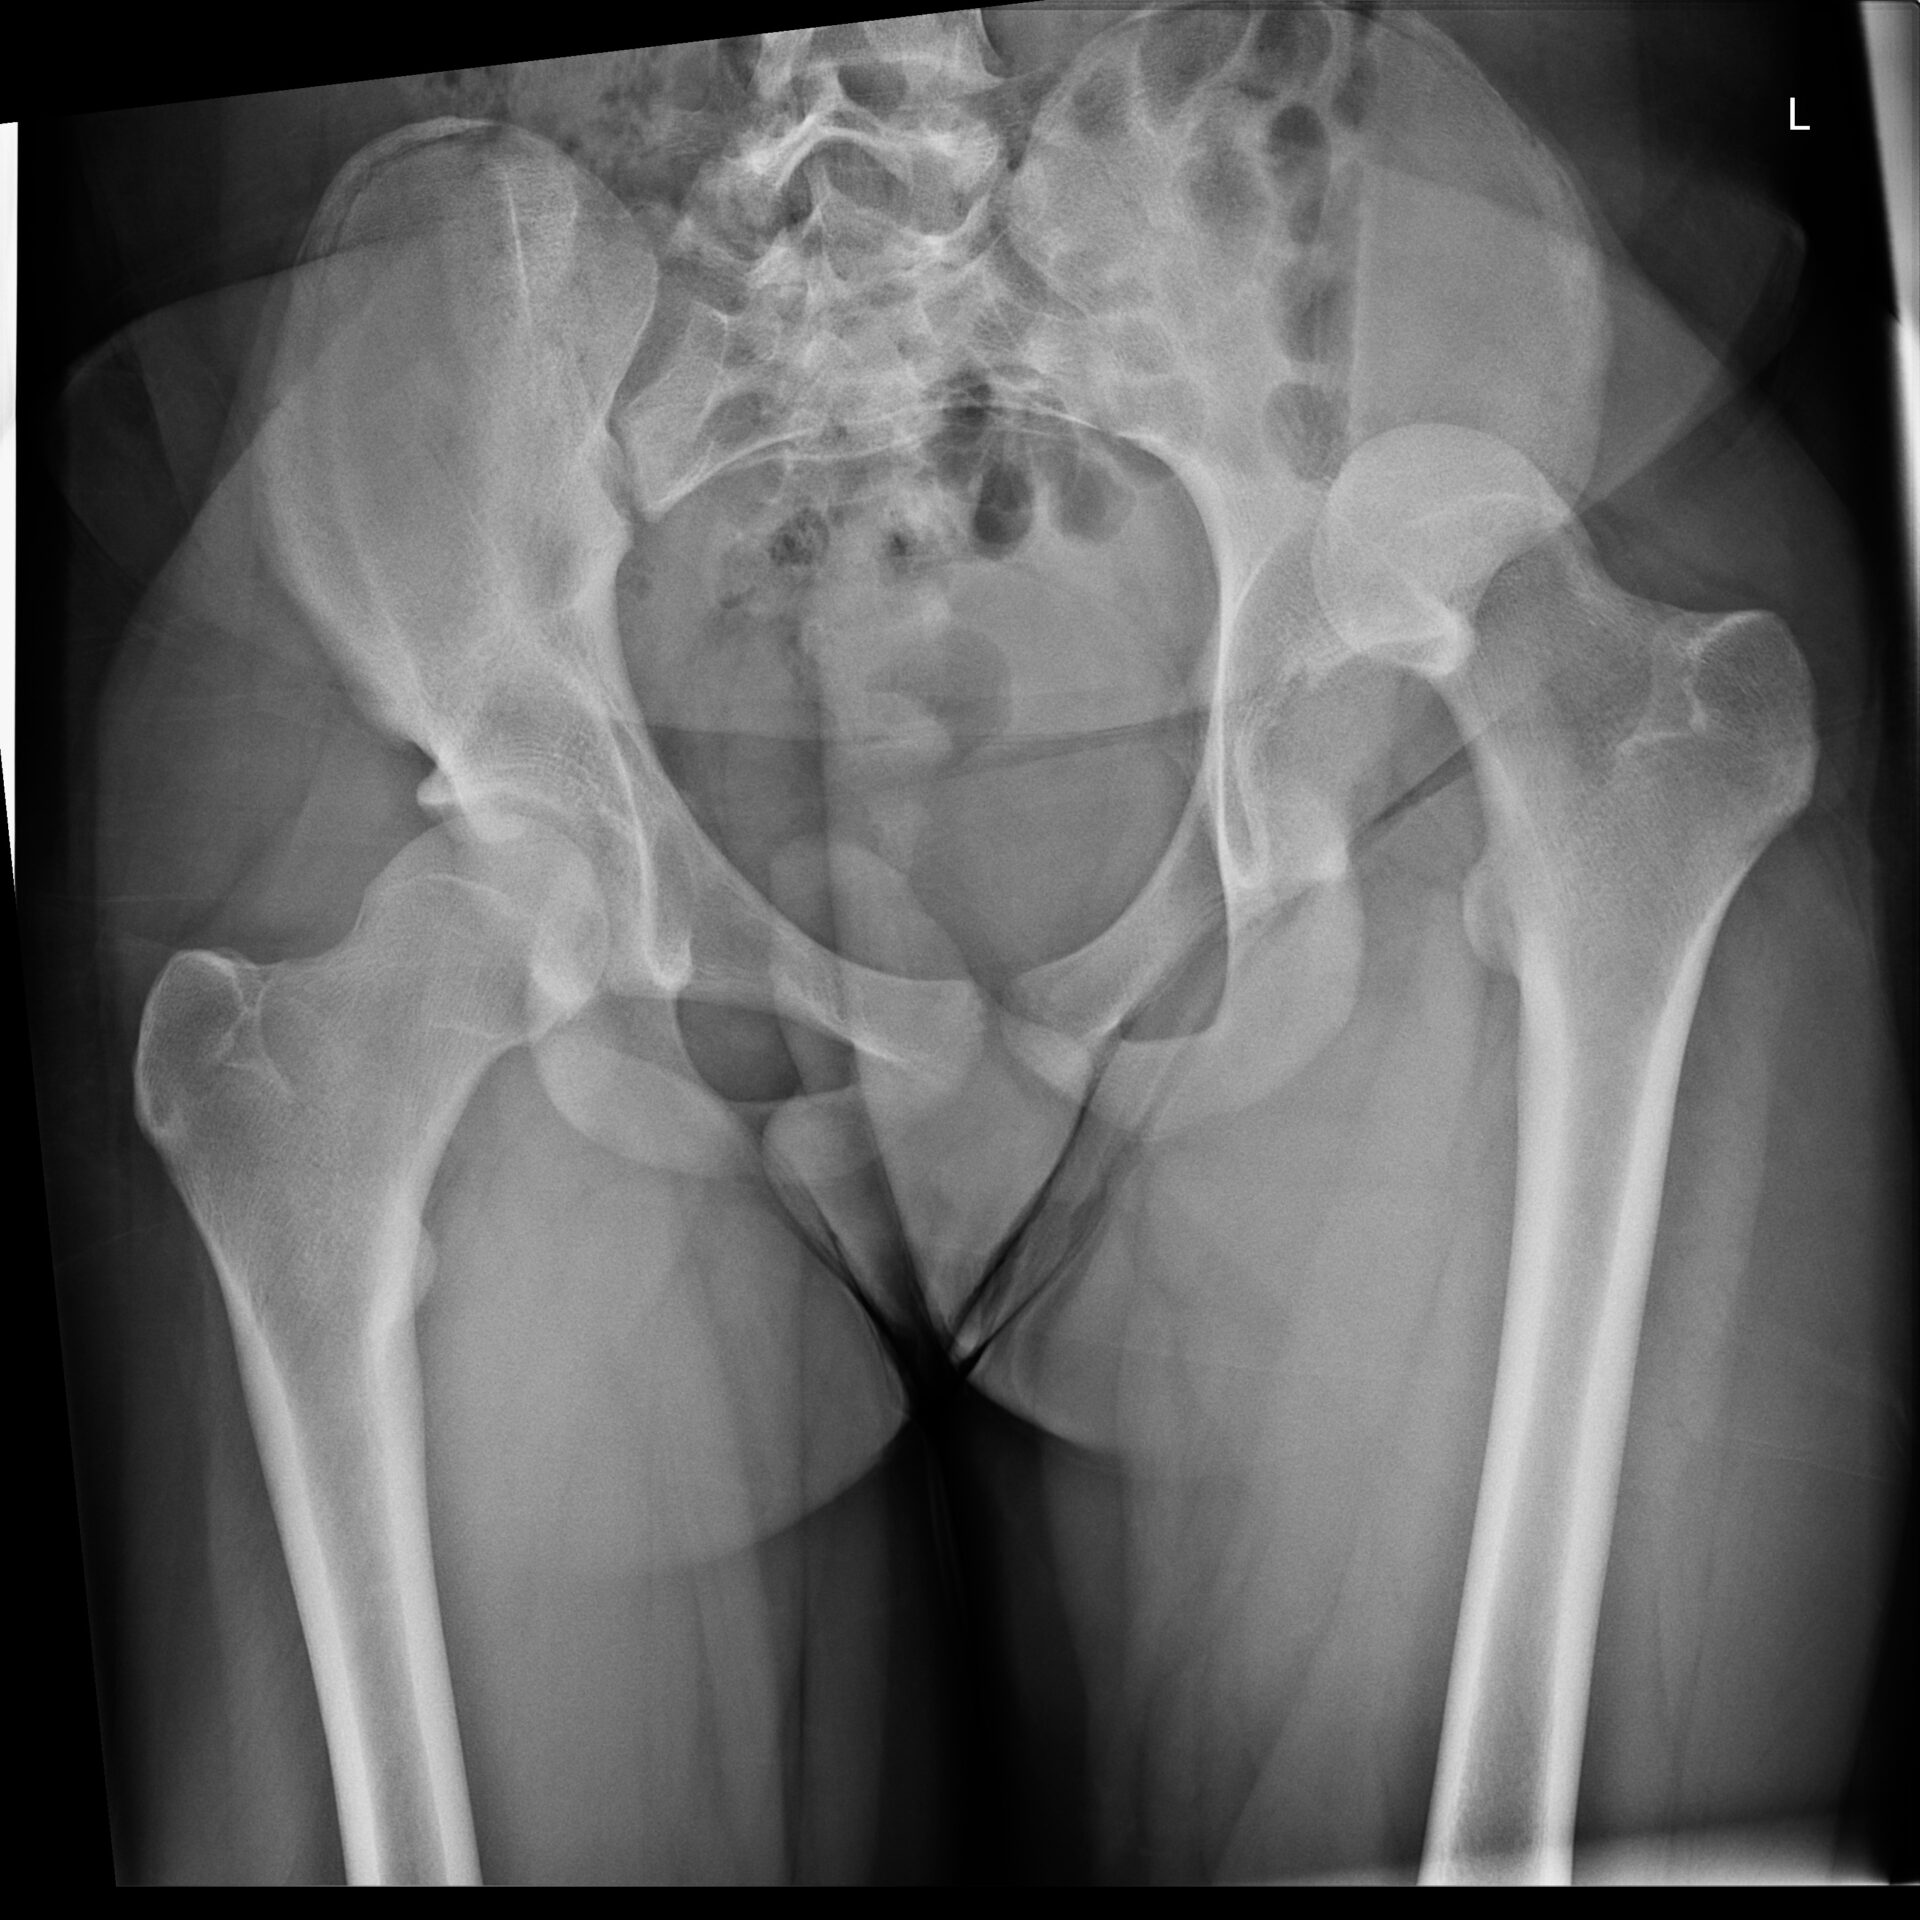

Praxisnahe Röntgenfälle, strukturierte Befundung, fundiertes Fachwissen. Lernen, üben, anwenden — mit echten Fällen aus der klinischen Praxis.

Die spezialisierte Lernplattform für Projektionsradiographie. Im Mitgliederbereich steht eine stetig wachsende Fallsammlung mit realen Röntgenbildern zur Verfügung — systematisch aufgebaut, mit strukturierter Befundung, Befundcheck und klinisch relevanten Zusatzhinweisen.